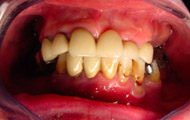

Exemple d’une réhabilitation complète implantaire

Situation clinique initiale

Situation clinique terminée